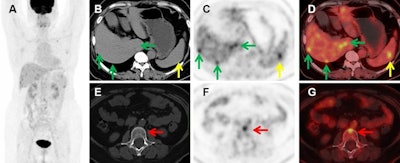

Images of a 56-year-old female with recurrence of choriodal melanoma two years after left eye enucleation. (A) Maximum intensity projection (MIP) images showed multiple metastatic lesions. B-D Axial CT (B), PET (C), and fused PET/CT (D) images showed liver metastasis (green arrows) and splenic metastasis (yellow arrows). E-G images showed an L2 vertebral metastasis without density changes (red arrows). Cancer ImagingF-18 FDG-PET/CT successfully detected metastases in 28 of the 31 patients (90.3%), including 26 of 29 (89.7%) patients with liver metastases, 15 of 15 (100%) patients with bone metastases, 10 of 10 (100%) patients with lung metastases, and nine of nine (100%) patients with lymph nodes metastases.